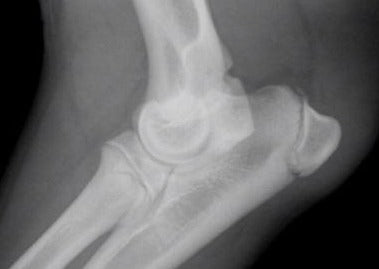

Nein, nicht immer! Beim Vergleich von CT und Röntgen zeigen sich bei beiden Verfahren Vor- und Nachteile. Relevanter als ein allgemeiner Vergleich sind jedoch die individuellen technischen Aspekte jede Untersuchung, die es zu erkennen und zu berücksichtigen gilt. So kann eine gute Röntgenuntersuchung diagnostisch wertvoller sein als eine schlechte CT-Untersuchung. Ein wichtiger Vorteil der Röntgendiagnostik liegt in der technisch einfachen Durchführbarkeit und Interpretation von Stressaufnahmen. Bei Stressaufnahmen wird indirekt die Stabilität und Funktionsfähigkeit von Bandstrukturen geprüft, indem Zug auf das jeweilige Band ausgeübt wird. Ein unphysiologisches Aufklappen und Divergieren von Gelenkspalten liefert den röntgenologisch indirekten Nachweis einer Bandläsion.